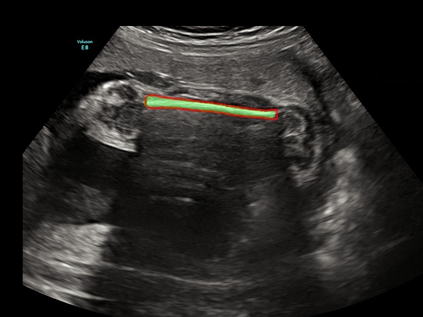

In this paper, we propose an end-to-end multi-task neural network called FetalNet with an attention mechanism and stacked module for spatio-temporal fetal ultrasound scan video analysis. Fetal biometric measurement is a standard examination during pregnancy used for the fetus growth monitoring and estimation of gestational age and fetal weight. The main goal in fetal ultrasound scan video analysis is to find proper standard planes to measure the fetal head, abdomen and femur. Due to natural high speckle noise and shadows in ultrasound data, medical expertise and sonographic experience are required to find the appropriate acquisition plane and perform accurate measurements of the fetus. In addition, existing computer-aided methods for fetal US biometric measurement address only one single image frame without considering temporal features. To address these shortcomings, we propose an end-to-end multi-task neural network for spatio-temporal ultrasound scan video analysis to simultaneously localize, classify and measure the fetal body parts. We propose a new encoder-decoder segmentation architecture that incorporates a classification branch. Additionally, we employ an attention mechanism with a stacked module to learn salient maps to suppress irrelevant US regions and efficient scan plane localization. We trained on the fetal ultrasound video comes from routine examinations of 700 different patients. Our method called FetalNet outperforms existing state-of-the-art methods in both classification and segmentation in fetal ultrasound video recordings.